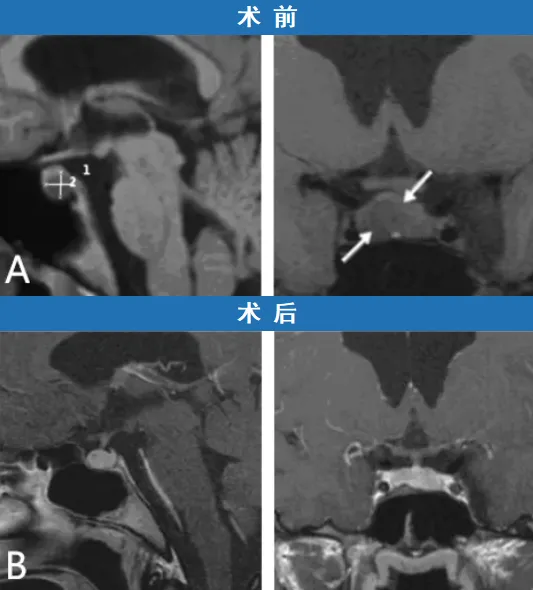

与小A的治疗经历不同,另一位患者小B则没有那么幸运。因闭经症状就诊的小B同样被诊断为泌乳素瘤,影像学检查发现肿瘤已将正常的垂体组织向左侧推移。施罗德教授首先建议小B接受多巴胺激动剂(Pravidel)治疗。然而,治疗后的随访显示,肿瘤不仅没有缩小,体积反而持续增大。

面对肿瘤进展的情况,小B一家无法再安心等待。他们绝不能坐视肿瘤继续生长并威胁女儿的生命安全。因此,施罗德教授决定调整治疗方案,放弃药物治疗,转为实施经鼻内镜手术。手术过程顺利,成功实现了泌乳素瘤的完全切除。术后一年的随访复查证实,肿瘤已被完整切除,小B的垂体功能维持正常。内分泌检查显示其泌乳素水平已恢复至正常范围,其余激素指标也无异常,无需进行外源性激素补充治疗。